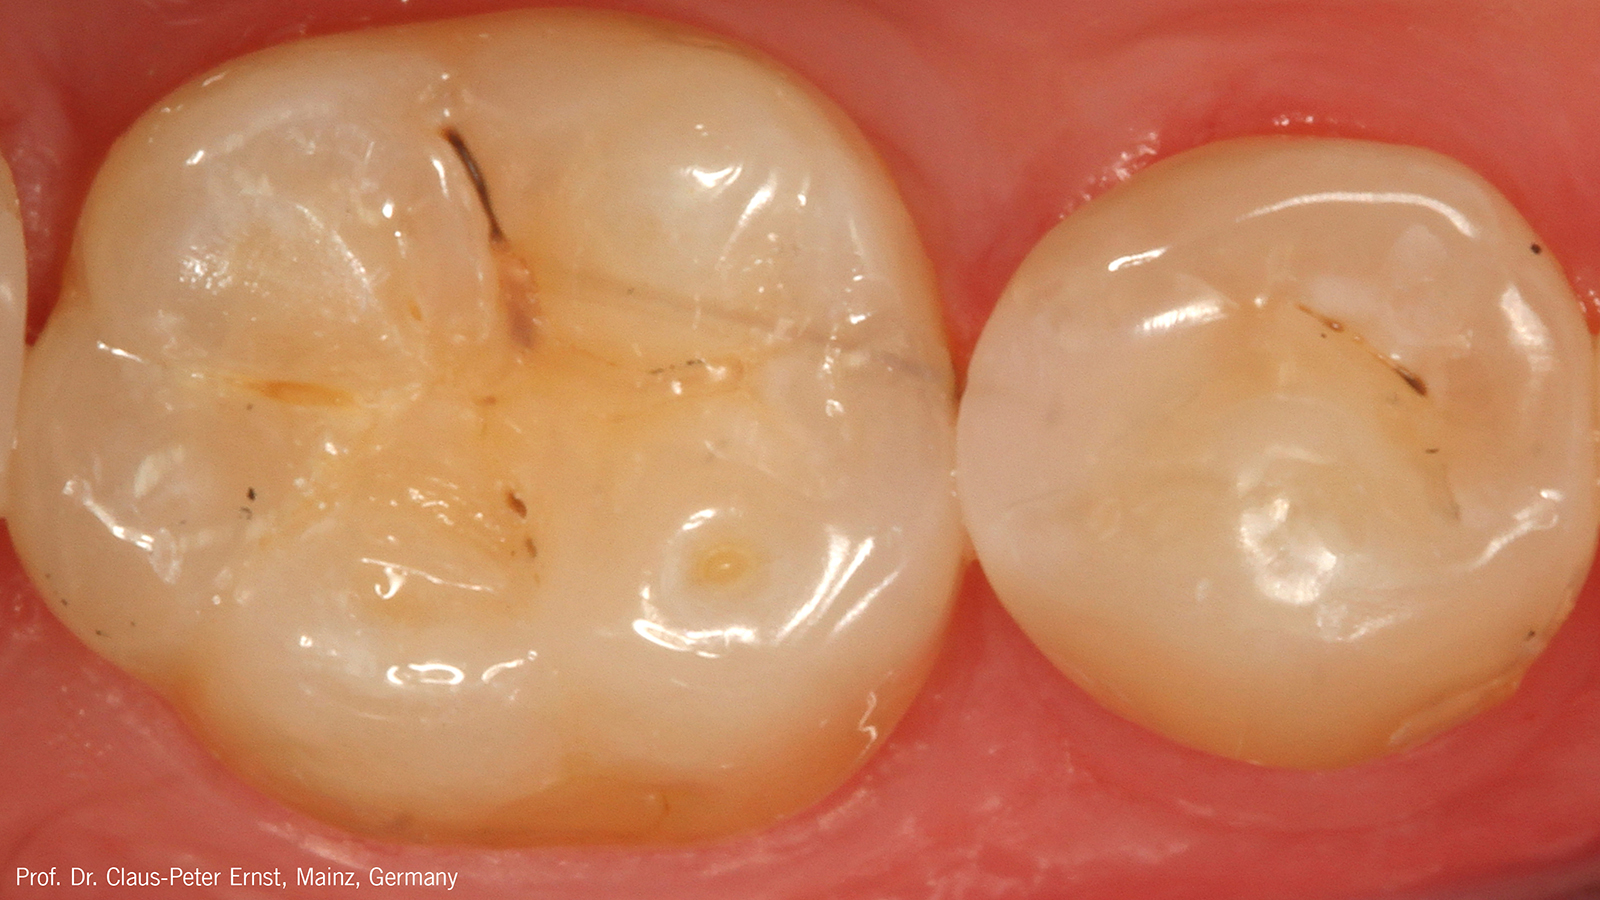

In case of severe discolourations, the tooth-coloured opaque shade Charisma Opal Flow OM (Opaque Medium) can be used. Alternatively, the white-opaque Charisma Opal Flow Baseliner can be used at the bottom of the cavity. This allows the coverage of discolourations and pre-vents the unnecessary removal of healthy tooth substance in case of a re-entry.

Does Charisma Bulk Flow ONE require an opaque blocker?